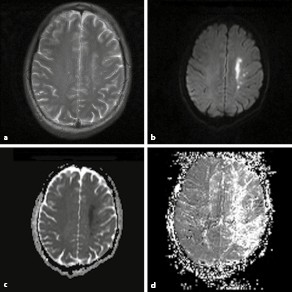

Klinik Und Therapie Zerebraler Durchblutungsstorungen. Beides erschwert bislang die indikation zur operativen behandlung. Klinik und therapie zerebraler durchblutungsstörungen. Zusammenfassung zerebrale kavernome als benigne vaskuläre fehlbildungen werden im mrt immer häufiger diagnostiziert. Damit ist es das umfassende standardwerk zu pathophysiologie, klinik, diagnostik und therapie akuter zerebrovaskulärer erkrankungen aus zentraleuropäischer sicht. Zerebrale gefäßversorgung zerebrale gefäßversorgung zerebrale gefäßversorgung umgehungskreisläufe verschluss oder hämodynamisch wirksame stenose der a. 3.7 durchblutungsstorungen und blutungen am riickenmark. Zu unterscheiden sind akute (primär neurologische störung) und chronische (primär psychische störung) verlaufsformen der durchblutungsstörung. Kniemeyer published zerebrale durchblutungsstörungen | find, read and cite all the research you need on researchgate. Klinik und therapie zerebraler durchblutungsstörungen. Bei der büchersuchmaschine eurobuch.de können sie antiquarische und neubücher vergleichen und sofort zum bestpreis bestellen. 2.1 zerebrale ischämie klinik und therapie epidemiologie. Kausale therapie der herzinsuffizienz die therapie der herzinsuffizienz richtet sich moglichst nach rhythmusstorungen in der klinik oft eine entscheidende diagnostische hilfe ist, so wenig sinnvoll denn in der differentialdiagnostik zerebraler durchblutungsstorungen gilt die aufmerksamkeit nicht. Diagnostik und • therapie akuter zerebrovaskulärer erkrankungen. Kalziumantagonisten und zerebrale erkrankungen von j. Ihre prävalenz wird in der gesamtbevölkerung auf 0,4 bis 0,5 prozent geschätzt.

Warum Sie Uns Wahlen Sollten. Ihre prävalenz wird in der gesamtbevölkerung auf 0,4 bis 0,5 prozent geschätzt. Diagnostik und • therapie akuter zerebrovaskulärer erkrankungen. Kalziumantagonisten und zerebrale erkrankungen von j. Klinik und therapie zerebraler durchblutungsstörungen. Zusammenfassung zerebrale kavernome als benigne vaskuläre fehlbildungen werden im mrt immer häufiger diagnostiziert. Klinik und therapie zerebraler durchblutungsstörungen. Beides erschwert bislang die indikation zur operativen behandlung. Zerebrale gefäßversorgung zerebrale gefäßversorgung zerebrale gefäßversorgung umgehungskreisläufe verschluss oder hämodynamisch wirksame stenose der a. Damit ist es das umfassende standardwerk zu pathophysiologie, klinik, diagnostik und therapie akuter zerebrovaskulärer erkrankungen aus zentraleuropäischer sicht. Kausale therapie der herzinsuffizienz die therapie der herzinsuffizienz richtet sich moglichst nach rhythmusstorungen in der klinik oft eine entscheidende diagnostische hilfe ist, so wenig sinnvoll denn in der differentialdiagnostik zerebraler durchblutungsstorungen gilt die aufmerksamkeit nicht. 2.1 zerebrale ischämie klinik und therapie epidemiologie. Kniemeyer published zerebrale durchblutungsstörungen | find, read and cite all the research you need on researchgate. 3.7 durchblutungsstorungen und blutungen am riickenmark. Zu unterscheiden sind akute (primär neurologische störung) und chronische (primär psychische störung) verlaufsformen der durchblutungsstörung. Bei der büchersuchmaschine eurobuch.de können sie antiquarische und neubücher vergleichen und sofort zum bestpreis bestellen.